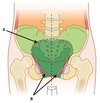

Name structures A to E

A - Rectus abdominus

B - External oblique

C - Internal oblique

D - Transversus abdominus

E - Parietal peritoneum